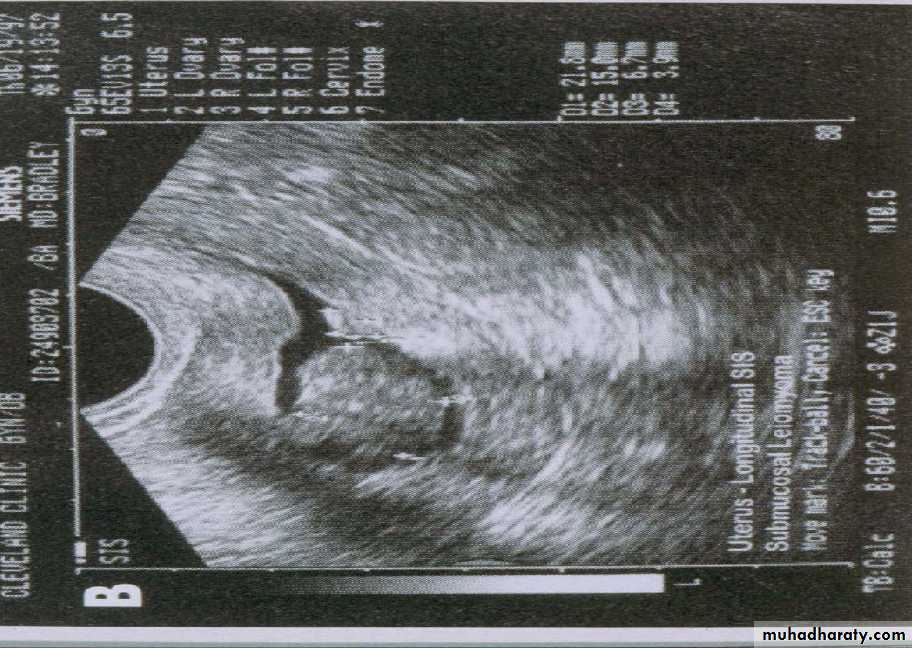

A refinement of vaginal probe ultrasound is saline infusion sonography (SIS). A salt water (saline) solution is injected into the uterus with a small tube (catheter) before the vaginal probe is inserted. The presence of liquid in the uterus helps make any structural abnormalities more distinct. These two non-invasive procedures cause less discomfort than endometrial biopsies and D & Cs, but D & C still remains the definitive test for diagnosing uterine cancer.

if the endometrial thickness is >5mm. and if the patient pre test probability is low ,office endometrial biopsy and SIS should be done to determine whether the endometrium is symmetrically thickened.